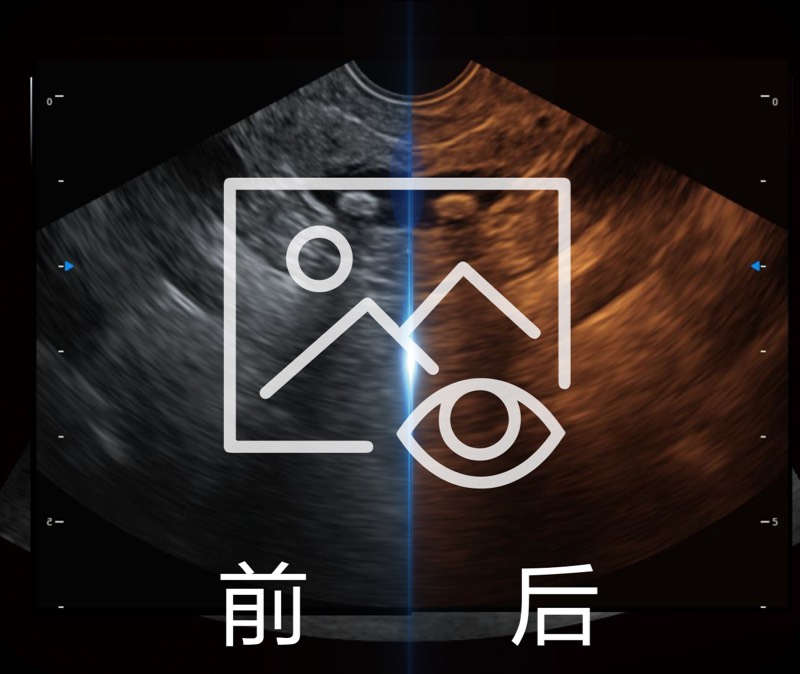

可人为将灰阶图像转变成彩色的显示方式,增强人眼对于不同回声强度的敏感度,主观上增加了图像分辨率